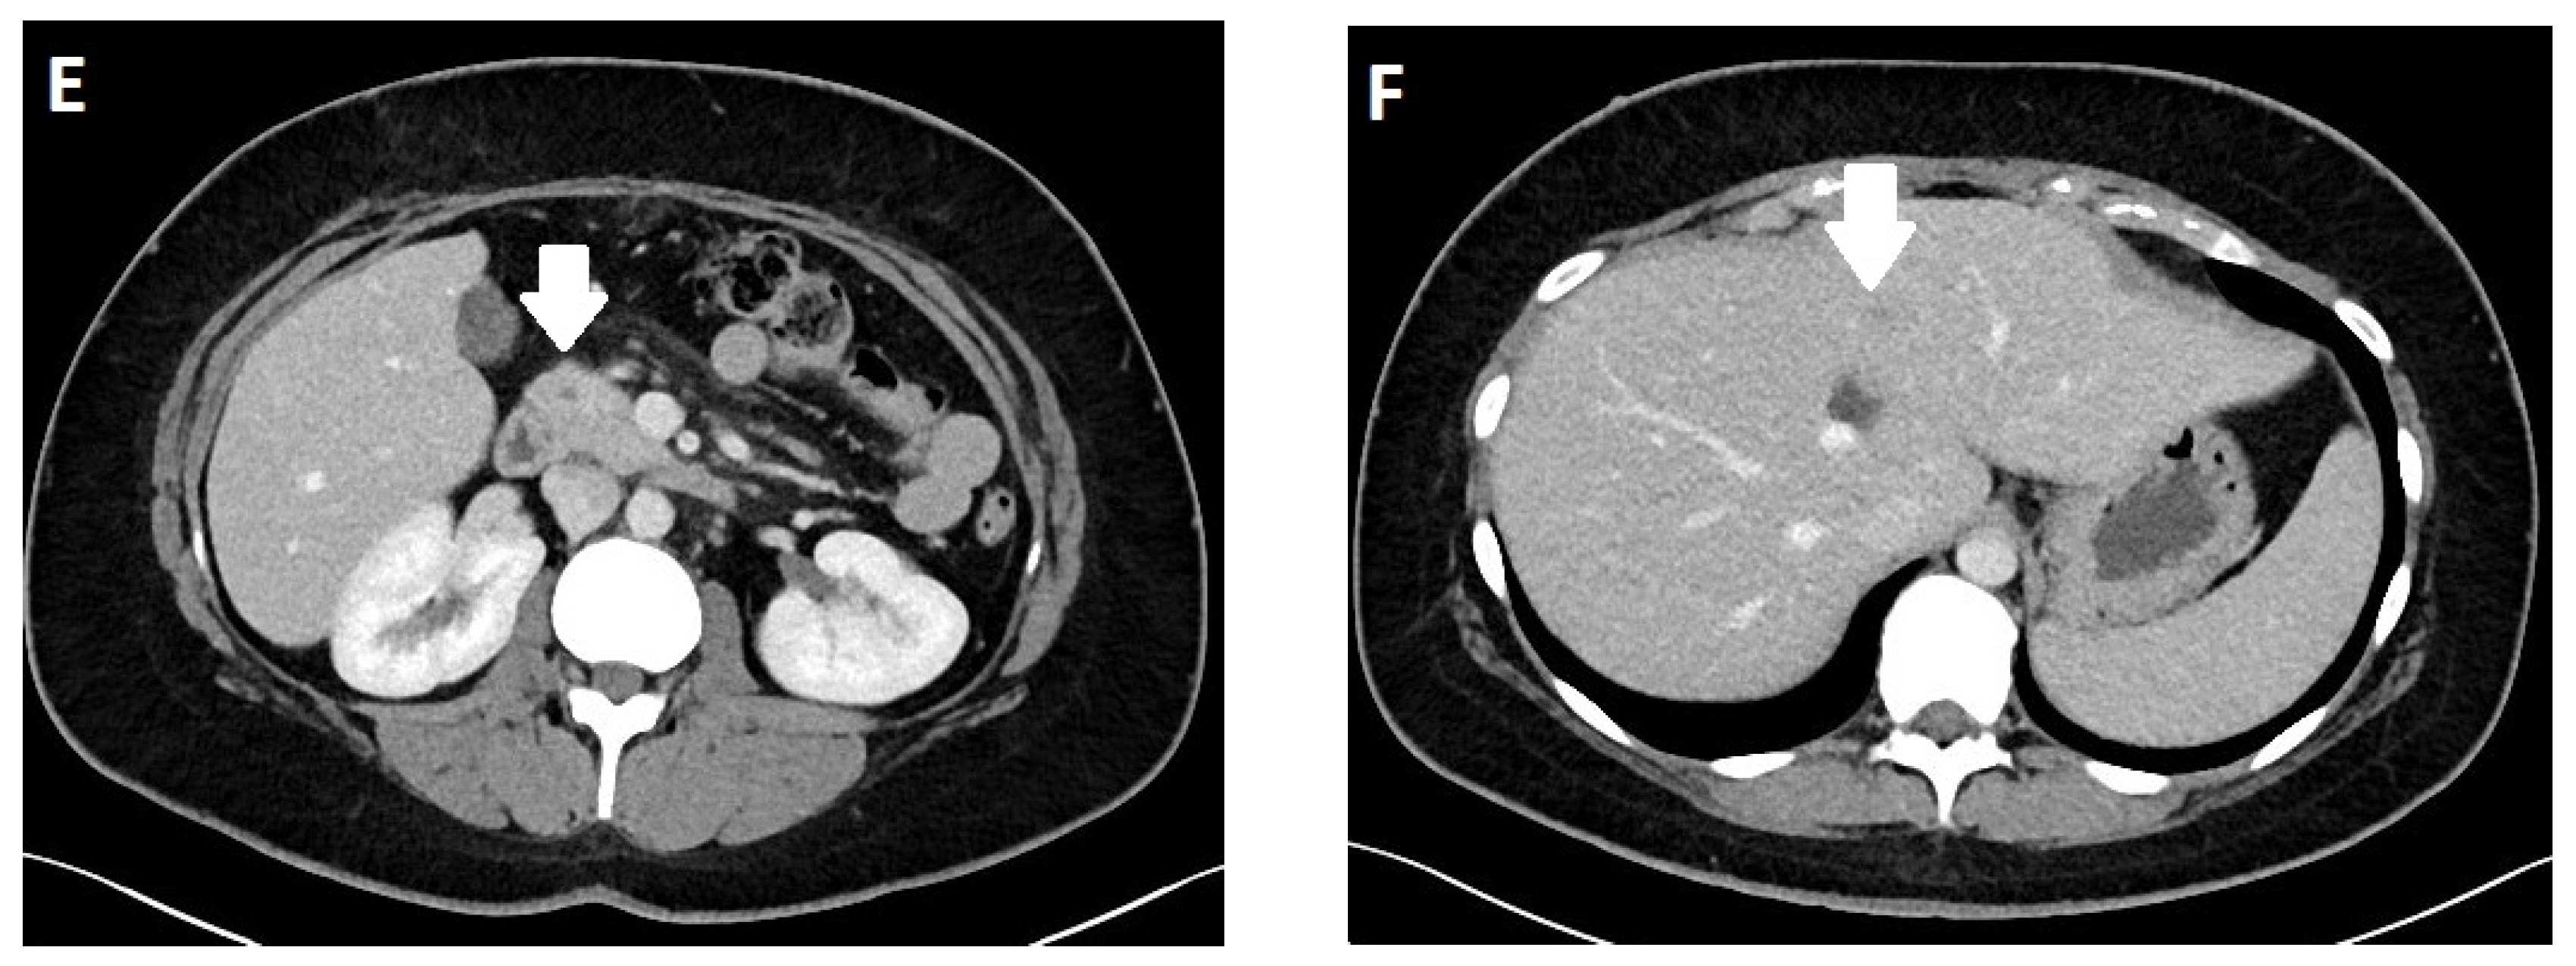

3.4. Imaging

PET/MRI